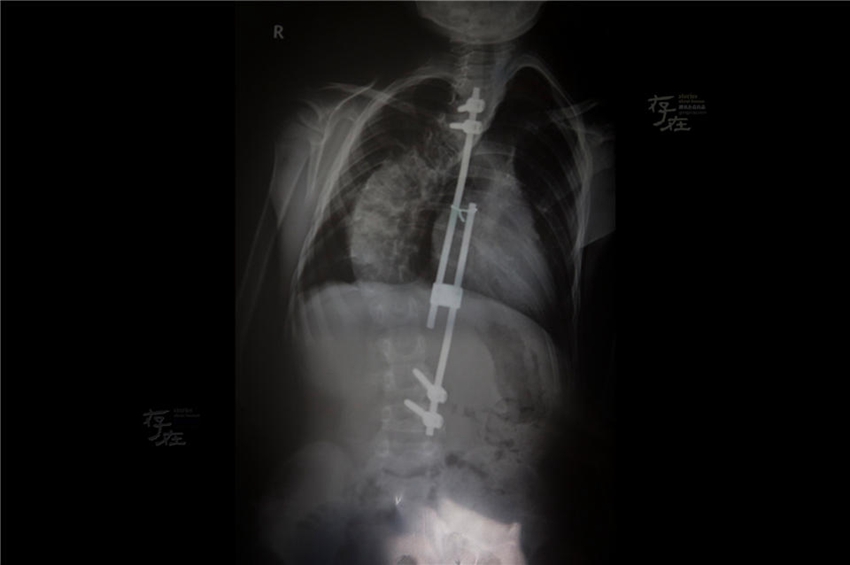

1? 26?, 8? ?? ??????(才仁東周)? X-?? ??? ??? ?? ??.